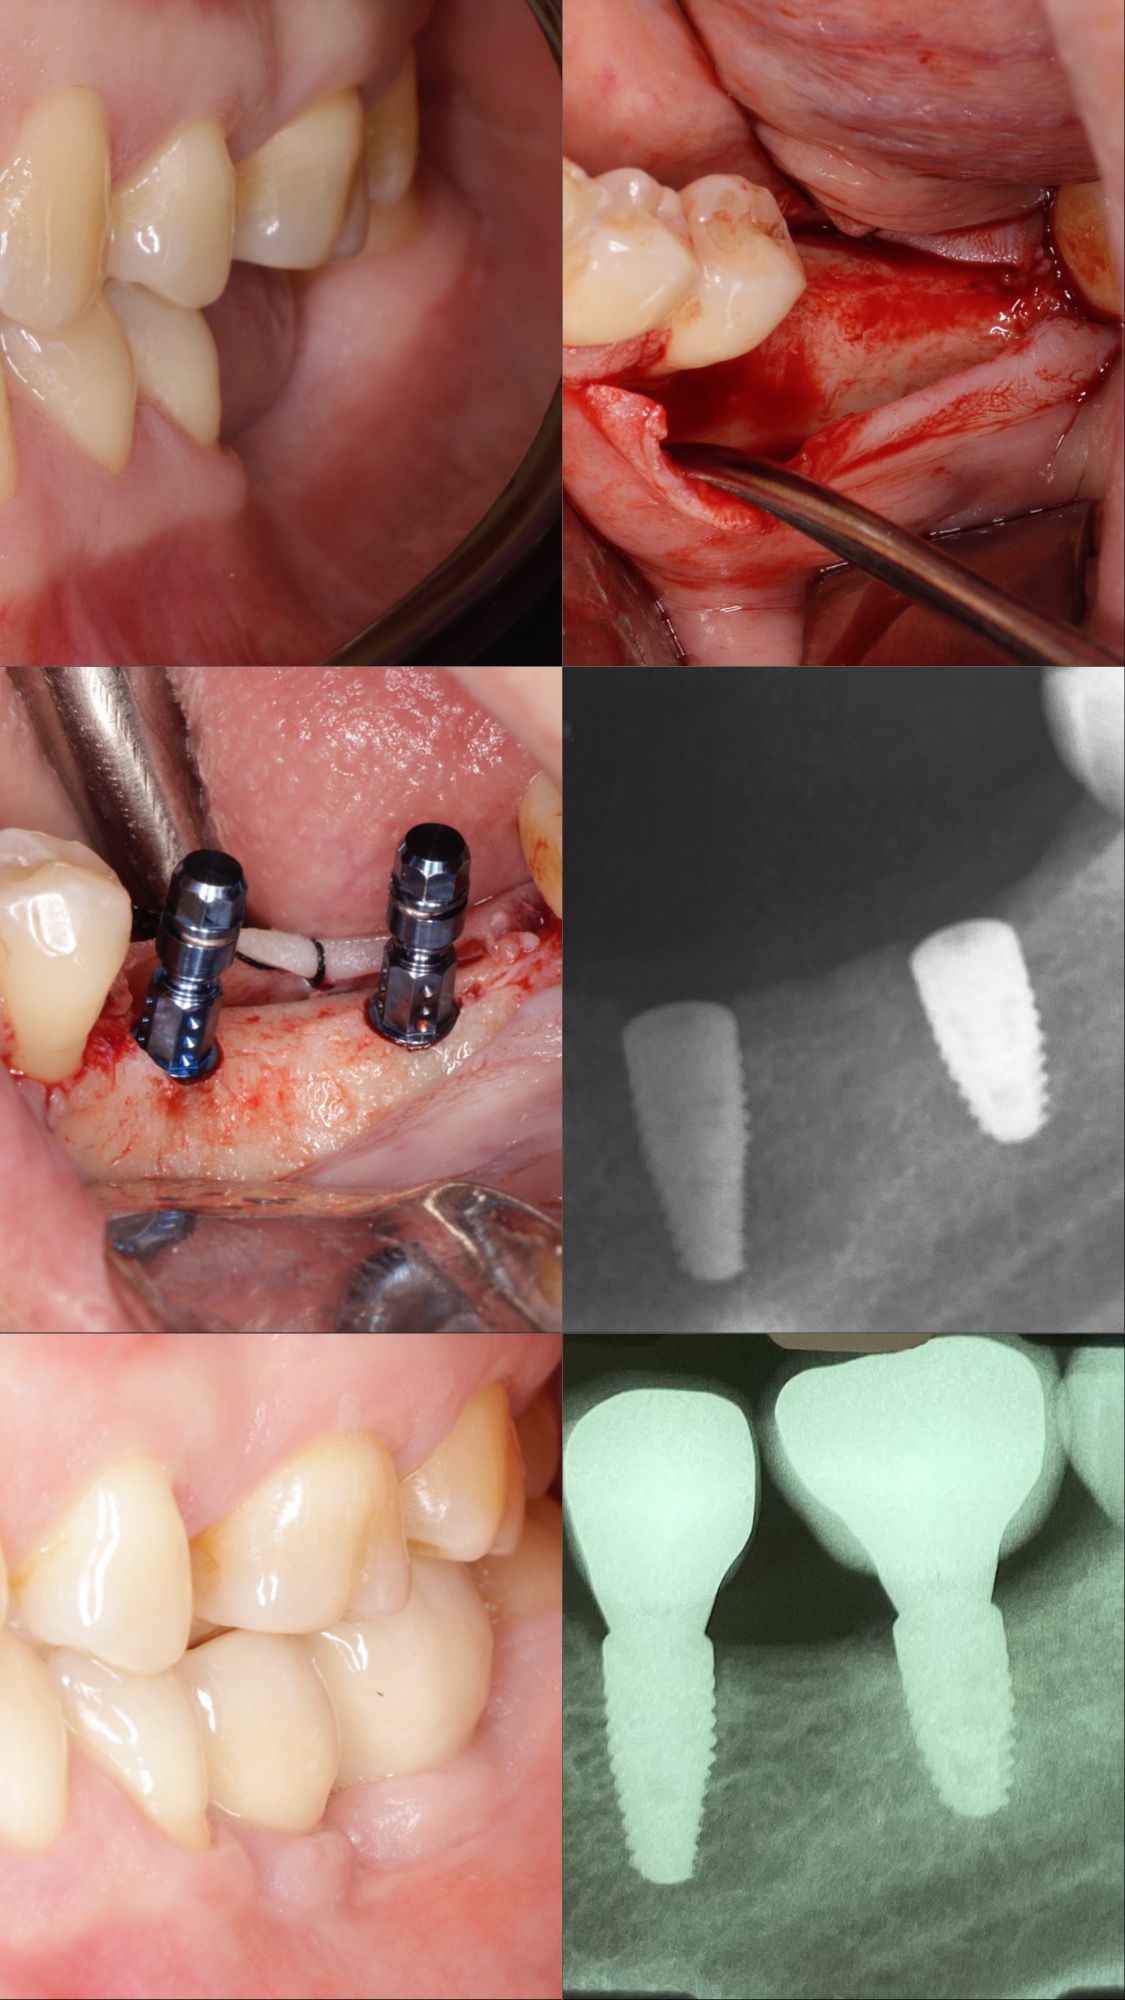

Diseño de Sonrisa con Implantes y Rehabilitación Oral

Descripción del caso:

Paciente tratado con cirugía de implante dental, finalizado con rehabilitación oral completa mediante coronas cerámicas y carillas estéticas, logrando un cambio integral en función y estética.

Procedimiento realizado en su totalidad por el Dr. Axel Paredes.

Antes y Después (imagen adjunta)

Temuco – Hochstetter 560, oficina 311